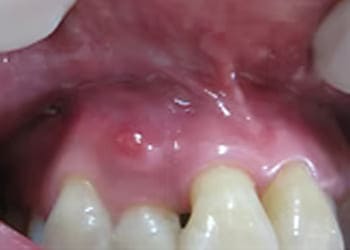

親知らずの治療は、基本的に抜歯が適応となります。

しかし、埋まった状態の親知らずの抜歯は難易度が高く、特に下顎の親知らずは顎の骨の中にある知覚神経(触覚や痛覚をつかさどる神経)や血管に近接しているため、抜歯後に唇や顔面皮膚の知覚異常が生じたり、抜歯部位から大量に出血したりする可能性があります。

もちろん、正常に萌出してきちんと噛めているものや、今後正常に萌出する可能性があるものについては、必ずしも抜歯する必要はありません。